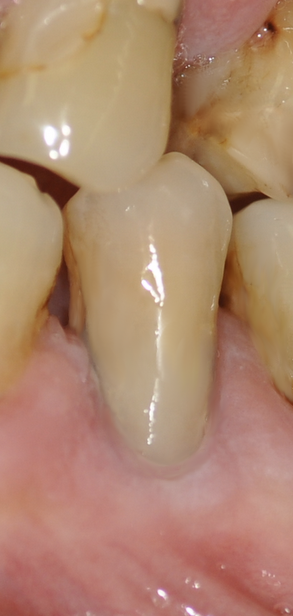

Il laser è una soluzione moderna per il trattamento chirurgico dei tessuti molli con una riduzione dello stress e del dolore avvertito dal paziente. Non sono necessari punti di sutura e non bisogna aspettare la guarigione del sito prima di intervenire sul difetto da restaurare.

L'azione battericida ed antisettica consente di ottenere una ferita pulita che va incontro a guarigione in tempo breve, senza particolare dolore avverto da parte dei pazienti.

- Innesto di gengiva: per l'incisione gengivale Gengivectomia e Gengivoplastica